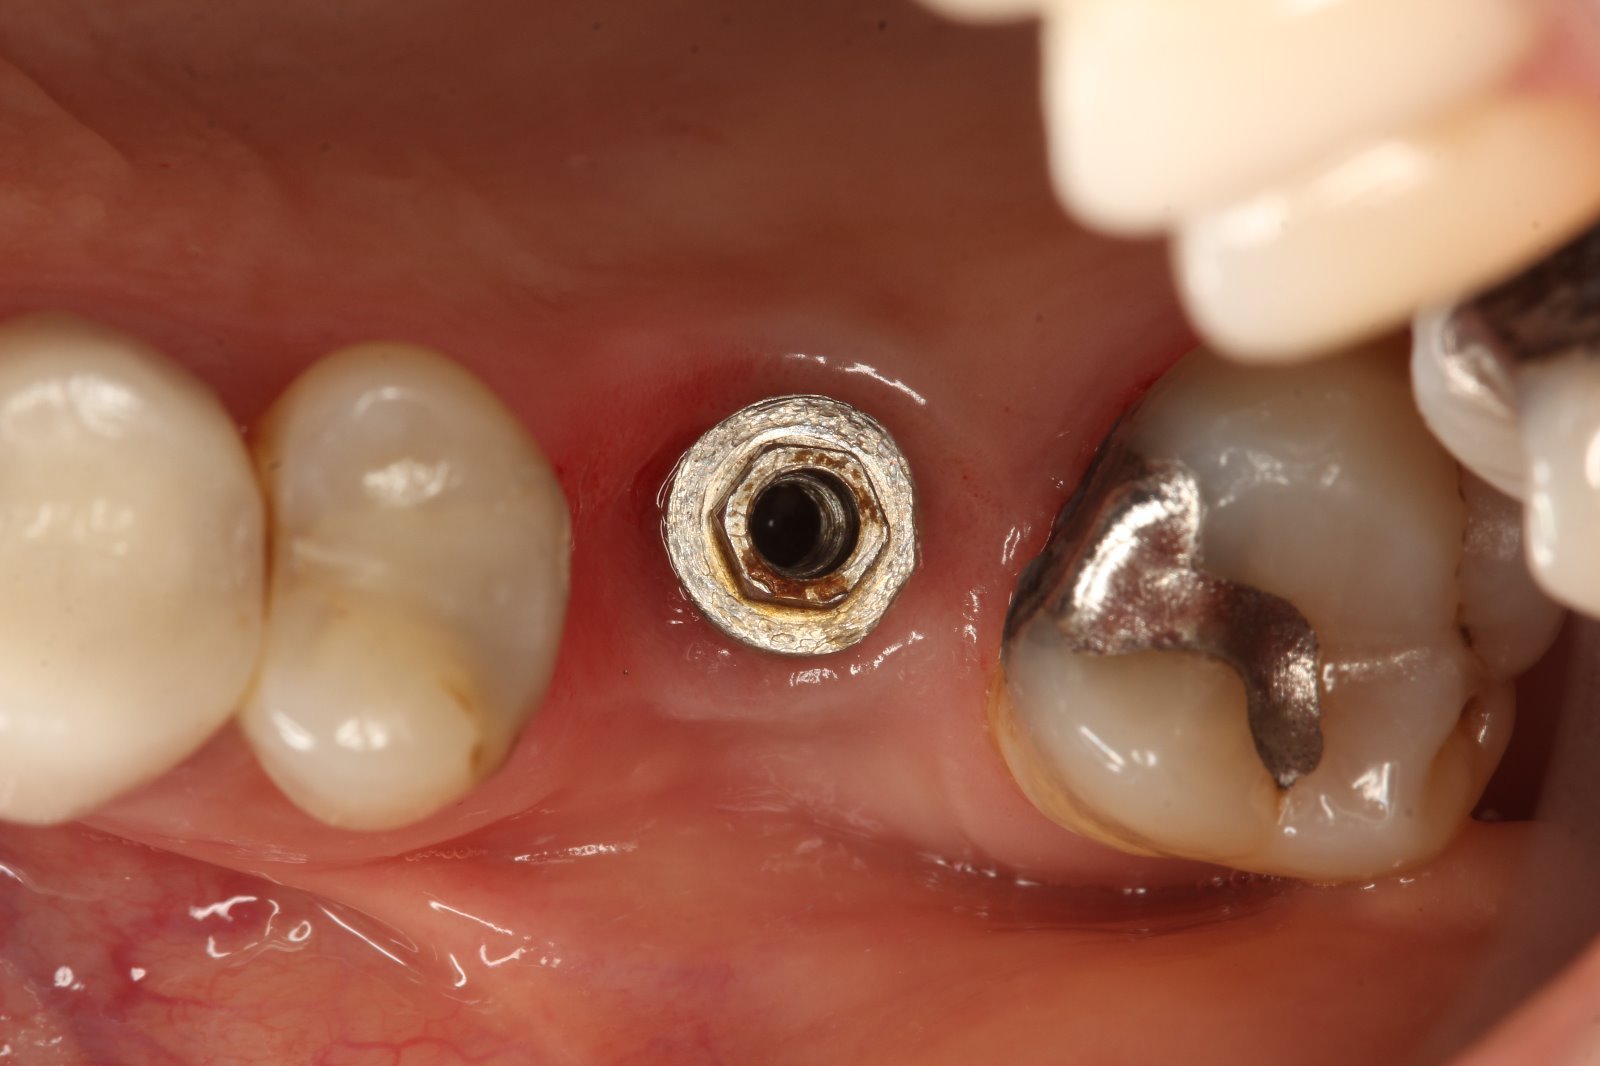

Buenas compañeros. Este caso es curioso porque entra el transfer de un sk2 por el hexágono pero el tornillo no. A ver si esta panorámica os sirve para identificarlo. Cuadrante [...]

Paciente que explanto el 15 por periimplantistis y movilidad pero que el 13 en principio lo voy a conservar , entonces necesito saber qué tipo de implante es el 13 [...]

Es conexión externa. Tiene puesto un tornillo para transformarlo en multiunit pero de 6 mm. Gracias